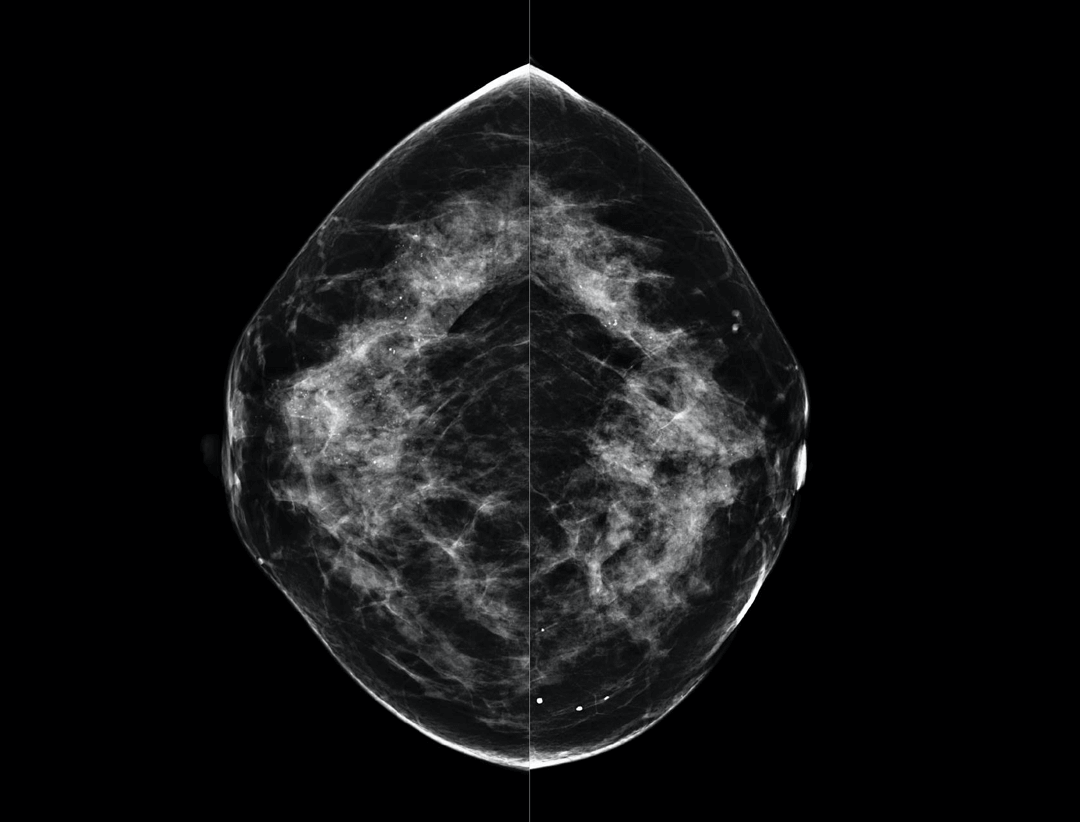

High Resolution Low Dose Imaging

Large coverage amorphous-silicon (a-Si) flat panel detector featuring an optimized active matrix array provides high spatial resolution and high image acquisition speed at a lower dose.

High performance tungsten target X-ray tube offers high resolution image for both dense and fatty breast densities.

Intelligntly detects breast density and thickness, then auto selects the appropriate filter combination.